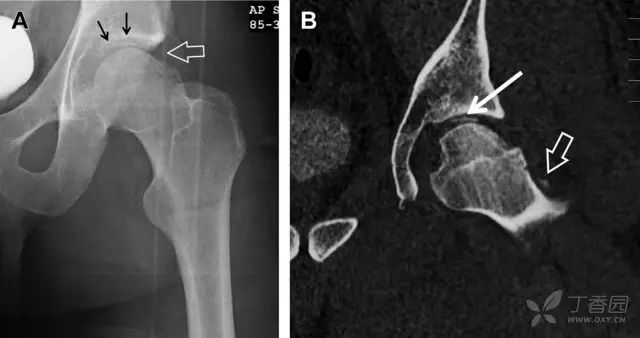

股骨头骨折常与髋关节脱位有关。需要注意的是那些既不是因剪力损伤也不是因直接暴力作用造成的骨折。这些类型的骨折可能十分轻微。提倡应用 CT 检查,不仅可诊断骨折,而且能评估关节内骨折碎片的位置(图 6)。

图 6 股骨颈骨折伴髋关节脱位。A 股骨头上外侧轮廓缺失(空箭头)注意嵌入上方关节间隙的骨折碎片(黑色箭头)B 冠状位 CT 多维重建(MPR)证实骨软骨碎片(白色箭头)和关节上方的另一个碎片(空箭头)

股骨颈骨折常发生在老年人,头下型骨折最常见,但是当股骨外旋或有明显的关节炎骨赘形成时,骨折较难发现。此外,肥胖和骨量减少增加髋部 X 片诊断难度,所以需格外注意。

因骨结构重叠影响,股骨转子骨折发生轻度移位时亦很难发现,加做一个不同角度的 X 线片有助于诊断(图 7)。

图 7 摔倒后股骨大转子骨折。A 正位片初步检查未发现明显骨折,进一步检查发现大转子上方皮质中断(箭头)。B 蛙式侧位片示骨折分离,尤其是后方(箭头)。初步检查时忽视了这一点,是因为股骨颈未能充分显示